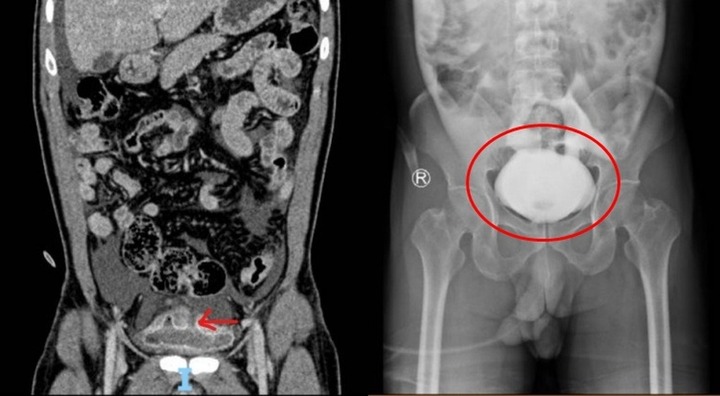

Bà ngoại dùng rượu pha sữa, cháu trai 1 tháng tuổi nhập viện trong tình trạng mơ màng. Ảnh minh họa.

Khi về đến nhà, cô kinh hoàng thấy con mình toàn thân đỏ ửng và rơi vào tình trạng lơ mơ. Đứa bé lập tức được đưa đến bệnh viện.

Rồi người bà cũng nhận ra sai lầm của mình sau khi ngửi bình sữa và vội vàng đưa cháu đến Bệnh viện Perrino gần đó. Em bé được cấp cứu khẩn cấp. Các bác sỹ bơm dạ dày và đặt nội khí quản. Ngày hôm sau, họ chuyển em bé đến bệnh viện nhi Giovanni ở Bari. Bé trai bị hôn mê do ngộ độc rượu, phải nằm trong phòng chăm sóc đặc biệt.